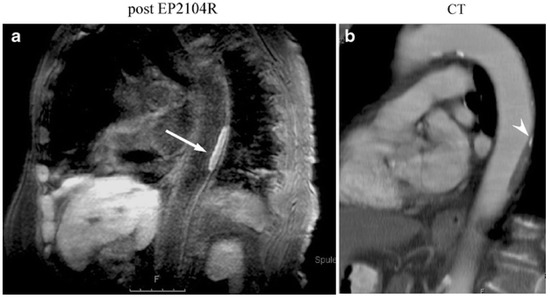

- Botnar, R.M.; Buecker, A.; Wiethoff, A.J.; Parsons, E.C.; Katoh, M.; Katsimaglis, G.; Weisskoff, R.M.; Lauffer, R.B.; Graham, P.B.; Gunther, R.W.; et al. In Vivo Magnetic Resonance Imaging of Coronary Thrombosis Using a Fibrin-Binding Molecular Magnetic Resonance Contrast Agent. Circulation 2004, 110, 1463–1466. [Google Scholar] [CrossRef] [PubMed]

- Spuentrup, E.; Botnar, R.M.; Wiethoff, A.J.; Ibrahim, T.; Kelle, S.; Katoh, M.; Özgun, M.; Nagel, E.; Vymazal, J.; Graham, P.B.; et al. MR imaging of thrombi using EP-2104R, a fibrin-specific contrast agent: Initial results in patients. Eur. Radiol. 2008, 18, 1995–2005. [Google Scholar] [CrossRef] [PubMed]

- Vymazal, J.; Spuentrup, E.; Cardenas-Molina, G.; Wiethoff, A.J.; Hartmann, M.G.; Caravan, P.; Parsons, E.C. Thrombus imaging with fibrin-specific gadolinium-based MR Contrast Agent EP-2104R Results of a Phase II Clinical Study of Feasibility. Investig. Radiol. 2009, 44, 697–704. [Google Scholar] [CrossRef] [PubMed]